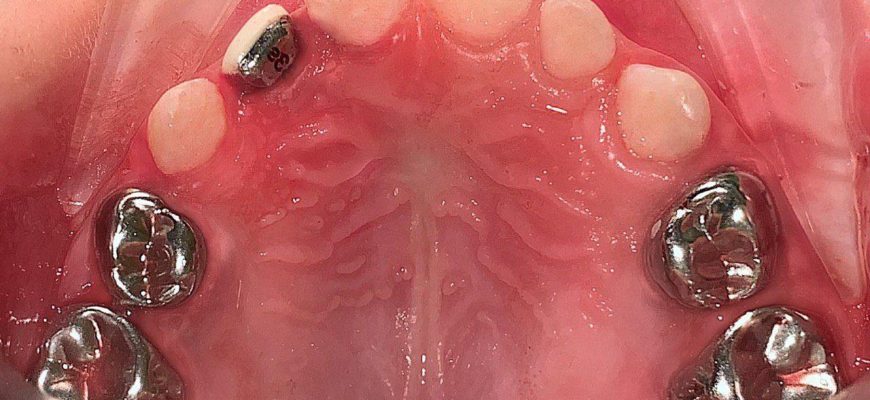

Современные методы лечения пульпита молочных зубов⁚ сохраняя здоровье малышей Пульпит молочных зубов – серьезное заболевание, требующее своевременного

Эффективные способы лечения пульпита молочных зубов у детей Пульпит молочных зубов – серьезное заболевание‚ требующее незамедлительного лечения.